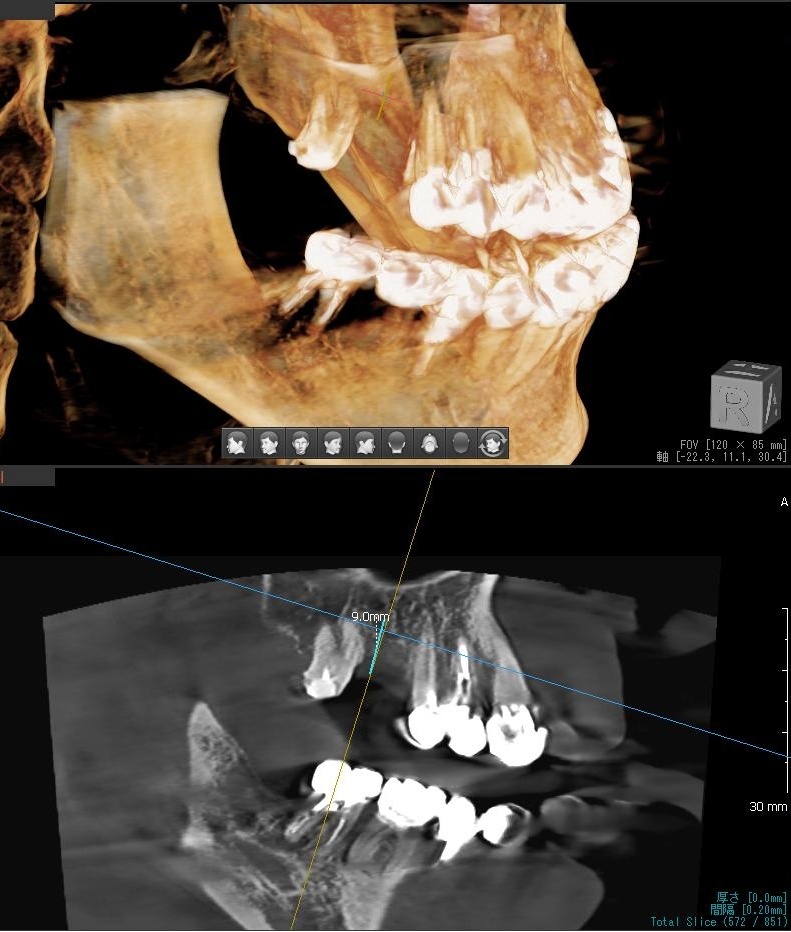

今回の患者様はインプラント植立を希望され、右上6番目の植立が決まりました。